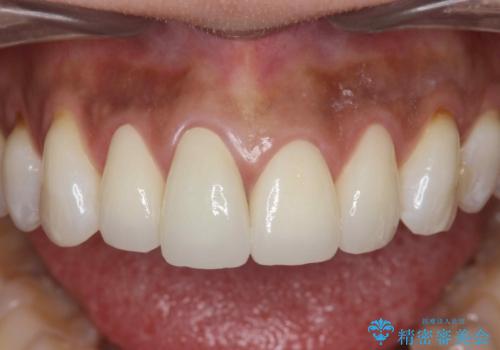

見た目が自然になり、色調も天然の歯とおなじような透明感のある色調が再現され、大変喜んでいただくことができました。